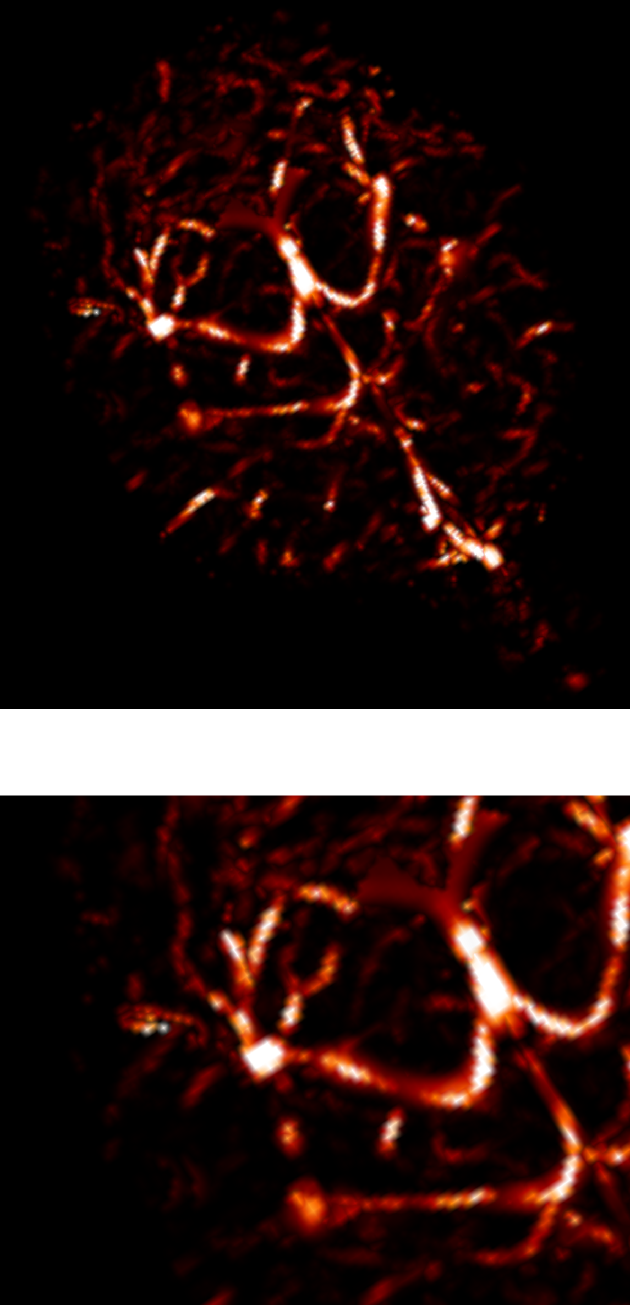

3.2.1 2D reconstructions

In this experiment, we considered a 2D -space () corresponding to an axial slice. We considered five sampling strategies, depicted in Fig. 2(first row): a classical EPI coverage used as reference (a); a TSP-based sampling trajectory parameterized using optimal control (b); two projected TSP-based trajectories, one with the same number of samples collected as in (b) () (c) and the other with the same scanning time as in (b) (62 ms) (d); a variable density spiral trajectory for comparison purpose in terms of time and sampling ratio (e).

As expected, the reconstruction results shown in Fig. 2(g,h) are really close, since the number of collected samples is the same, and the sampling densities are similar. However, in this comparison the gain in traversal time is significant (one half). In contrast, the longer and smoothed TSP depicted in Fig. 2(d) allows us to improve image reconstruction (1 dB gain) as illustrated by Fig. 2(i) while keeping the same acquisition time as in Fig. 2(b). For comparison purposes, we implemented spiral acquisition which consists of replacing steps (ii)-(iii) in the above mentioned sampling strategy by a spiral with density proportional to , projected onto the set of constraints. This strategy doubles the acquisition time (118 ms compared to 62 ms) whereas the acceleration factor was larger ( vs. ). In this experimental context (regridding and variable density spiral), the spiral is not appealing compared to EPI acquisition, since it is time consuming and degrades the image quality.

In each of these reconstructions, the major vessels can be recovered, although the smallest ones can only be seen for . Finally, the best compromise between acquisition time and reconstruction quality is achieved using the specific combination of TSP-based sampling and our projection algorithm onto the set of constraints shown in Fig. 2(d).

| (a) | (b) | (c) | (d) | (e) |

|---|---|---|---|---|

|

Sampling schemes

![]() |

| ms () | ms () | ms () | ms () | ms () |

| (f) | (g) | (h) | (i) | (j) |

Reconstructed slices

| Reference | PSNR = 25.9 dB | PSNR = 25.5 dB | PSNR = 26.9 dB | PSNR = 26.8 dB |